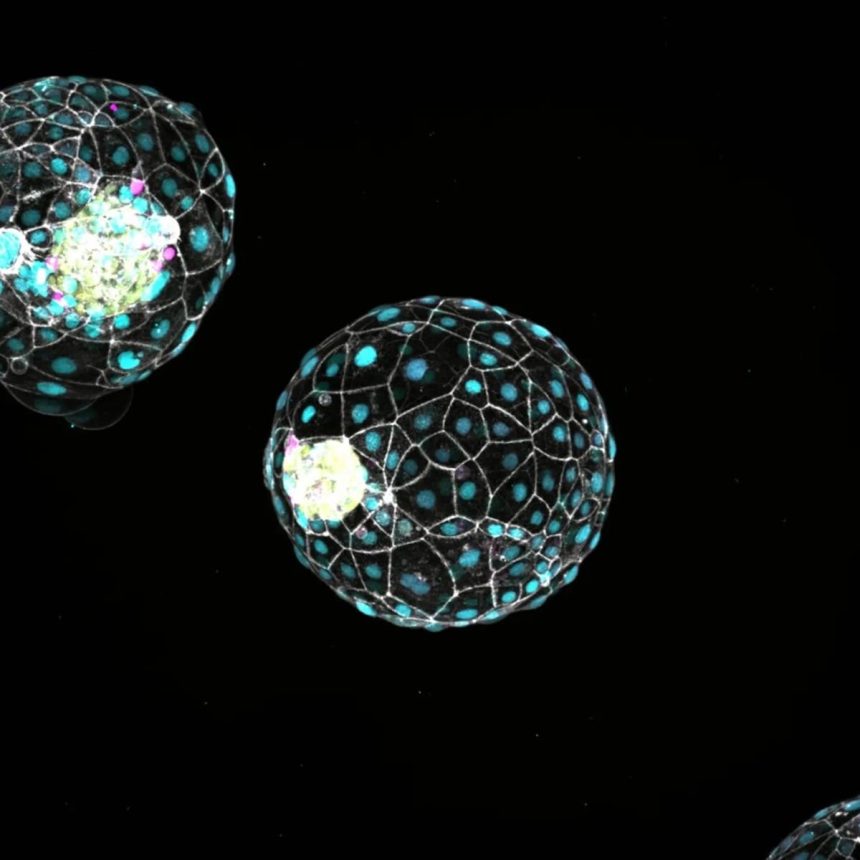

Fueyo ve ekibi, döllenmeden yaklaşık beş gün sonra gerçekleşen embriyonik gelişim evresi olan blastokisti taklit edecek şekilde düzenlenmiş kök hücreleri kullandı.

Bu üç boyutlu model (blastoid), embriyonun rahim duvarına yerleşmesinden hemen önceki gelişim aşamasını taklit ediyor.

Araştırmacılar, LTR5Hs olarak bilinen kalıntı virüs genleri grubunu etkisiz hâle getirdiklerinde, embriyo modeli ya düzensiz bir hücre yığınına dönüştü ya da öldü.

LTR5Hs genleri olmadan, üç tabakalı blastoidin orta tabakası (epiblast) düzgün şekilde oluşamadı.

Yapılan çalışma sayesinde LTR5Hs aktivitesinin, blastoid oluşumu ve hücre soyunun kimliğinin belirlenmesi için gerekli olduğu ortaya konmuş oldu.